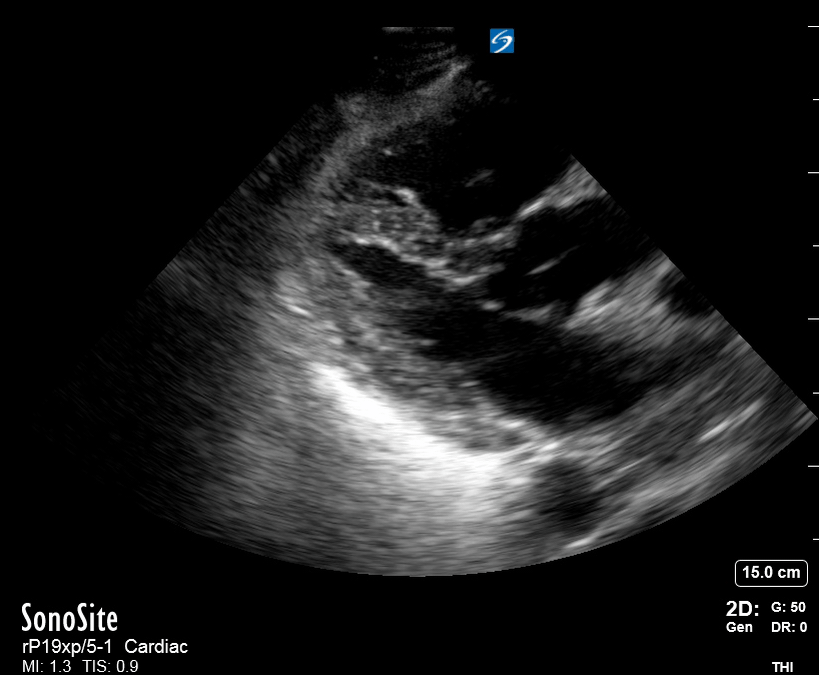

Effusion: is there a pericardial or pleural effusion?

Pericardial effusion is a continuum and can potentially evolve into haemodynamic collapse. Tamponade physiology is detectable earlier with ultrasound than with traditional physical examination, and it has been demonstrated that PoCUS improves mortality in penetrating cardiac trauma. Timely and accurate diagnosis is, therefore, vital.

THE VIEWS

The subxiphoid view is the most reliable for detecting pericardial effusion. Still, it is ideal to obtain different views not to miss a focal effusion as small amounts of fluid can lead to tamponade physiology. Tamponade does not link strictly to the size of the effusion, but correlates more with the speed of onset, causes, and haemodynamic effects.

PITFALLS & PLEURAL EFFUSIONS

A common error is to confuse a pericardial fat pad with effusion. Fatty tissue has a heterogeneous echotexture, moving in coordination with the myocardium, and it cannot be tracked around the heart, especially posteriorly and to the apex. Another pitfall is misinterpreting a pleural effusion as a pericardial effusion. However, they can be differentiated by their relationship to the descending aorta. Pericardial effusion may be seen between the aorta and the LV free wall, whereas pleural effusions are posterior to the descending aorta. Lastly, other causes, namely hypovolaemia and large pleural effusions, can cause RA and RV collapse.

CARDIAC TAMPONADE

Progressively rising pressure translates into evolving tamponade, and this accompanies a series of ultrasound findings:

Initially, the RA collapses during ventricular systole (closed AV valves).

Followed by RV collapse in ventricular diastole (open AV valves).

Ultimately leading to LV collapse.

In addition, the presence of a non-collapsible, plethoric IVC is one of the most sensitive signs of tamponade, and a finding easy to visualise. Conversely, a pericardial effusion in a haemodynamically stable patient with a collapsible IVC is unlikely to represent tamponade.